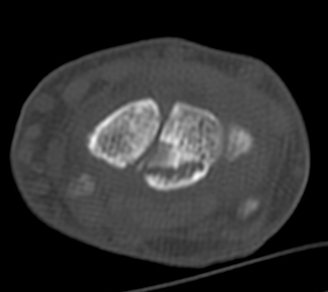

ÃÊÀ½ÆÄ°Ë»ç : ¼Õ¸ñ ¹èÃø Á¾´Ü¸é°Ë»ç¿¡¼­ ¼ö±Ù°üÀý³» ¼ö¾×Àú·ù°¡ °üÂûµÊ(»çÁø 1).

¼Õ¸ñ ÀåÃø Á¾´Ü¸é°Ë»ç¿¡¼­ ¿ù»ó°ñ °ñ±ØÀÌ °üÂûµÊ(»çÁø 2).

ÄÄÇ»ÅÍ ÃÔ¿µ :  ¿ù»ó°ñÀÇ ºÐ¼â°ñÀýÀÌ °üÂûµÊ(»çÁø 5, 6, 7, 8).